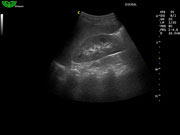

Отображение гармоники ткани (THI)

Не только улучшает пространственное разрешение, но и значительно повышает контраст изображения. Специально для полных пациентов, чтобы врач более точно ставил диагноз.

- Улучшает пространственное и контрастное разрешение изображения.

- Доступно для всех датчиков.

- Возможность выбора до 5 полос частот.